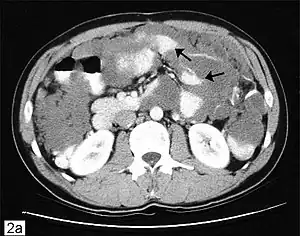

CT scanning is preferred to assess the extent of the tumor in the abdominopelvic cavity, though magnetic resonance imaging can also be used.[28] CT scanning can also be useful for finding omental caking or differentiating fluid from solid tumor in the abdomen, especially in low malignant potential tumors. However, it may not detect smaller tumors. Sometimes, a chest x-ray is used to detect metastases in the chest or pleural effusion. Another test for metastatic disease, though it is infrequently used, is a barium enema, which can show if the rectosigmoid colon is involved in the disease. Positron emission tomography, bone scans, and paracentesis are of limited use; in fact, paracentesis can cause metastases to form at the needle insertion site and may not provide useful results.[29] However, paracentesis can be used in cases where there is no pelvic mass and ascites is still present.[29] A physician suspecting ovarian cancer may also perform mammography or an endometrial biopsy (in the case of abnormal bleeding) to assess the possibility of breast malignancies and endometrial malignancy, respectively. Vaginal ultrasonography is often the first-line imaging study performed when an adnexal mass is found. Several characteristics of an adnexal mass indicate ovarian malignancy; they usually are solid, irregular, multilocular, and/or large; and they typically have papillary features, central vessels, and/or irregular internal septations.[31] However, SCST has no definitive characteristics on radiographic study.[33]

In advanced cancers, where complete removal is not an option, as much tumor as possible is removed in a procedure called debulking surgery. This surgery is not always successful, and is less likely to be successful in women with extensive metastases in the peritoneum, stage- IV disease, cancer in the transverse fissure of the liver, mesentery, or diaphragm, and large areas of ascites. Debulking surgery has usually only been done once[28] but a recent study has shown a longer overall survival in recurrent ovarian cancer when surgery combined with chemotherapy was performed compared to treatment with chemotherapy alone.[95] Computed tomography (abdominal CT) is often used to assess if primary debulking surgery is possible, but low certainty evidence also suggests fluorodeoxyglucose‐18 (FDG) PET/CT and MRI may be useful as an addition for assessing macroscopic incomplete debulking.[96] More complete debulking is associated with better outcomes: women with no macroscopic evidence of disease after debulking have a median survival of 39 months, as opposed to 17 months with less complete surgery.[26] By removing metastases, many cells that are resistant to chemotherapy are removed, and any clumps of cells that have died are also removed. This allows chemotherapy to better reach the remaining cancer cells, which are more likely to be fast-growing and therefore chemosensitive.[29]